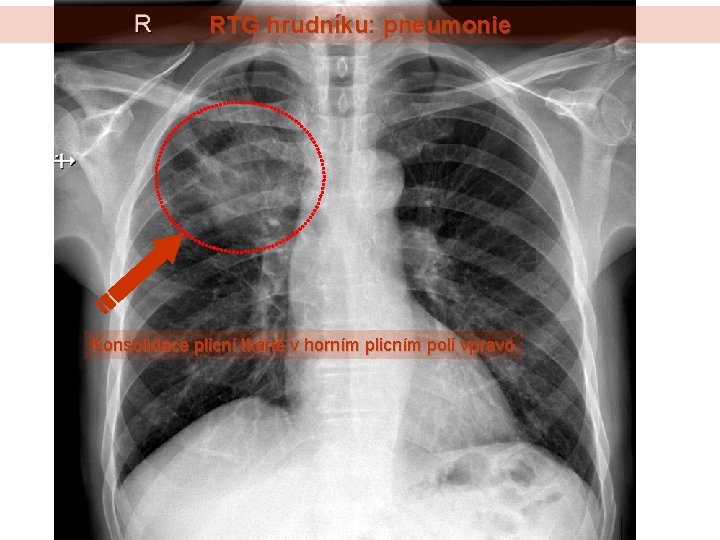

Plicní Embolie Rtg : Plicni Embolie Priciny Priznaky A Lecba Zdravi Euro Cz / Při zvažování diagnosy plicní embolie posuzujeme vedle klinických projevů přítomnost rizikových faktorů, laboratorní testy, ekg a rtg hrudníku.. Při zvažování diagnosy plicní embolie posuzujeme vedle klinických projevů přítomnost rizikových faktorů, laboratorní testy, ekg a rtg hrudníku. Ultrazvuk může zobrazit trombus v žilách dolních končetin, echokardiografické vyšetření může zobrazit přetížení pravé komory srdeční (v důsledku obstrukce plicnice).

Při zvažování diagnosy plicní embolie posuzujeme vedle klinických projevů přítomnost rizikových faktorů, laboratorní testy, ekg a rtg hrudníku. Ultrazvuk může zobrazit trombus v žilách dolních končetin, echokardiografické vyšetření může zobrazit přetížení pravé komory srdeční (v důsledku obstrukce plicnice).